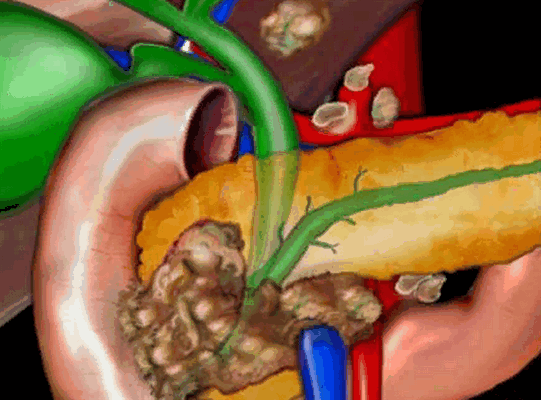

На рисунке неоперабельная опухоль головки поджелудочной железы, блокирующая общий желчный и панкреатические протоки, окружающее верхнюю брыжеечную вену; видно увеличение регионарных лимфоузлов, единичные метастазы в печени